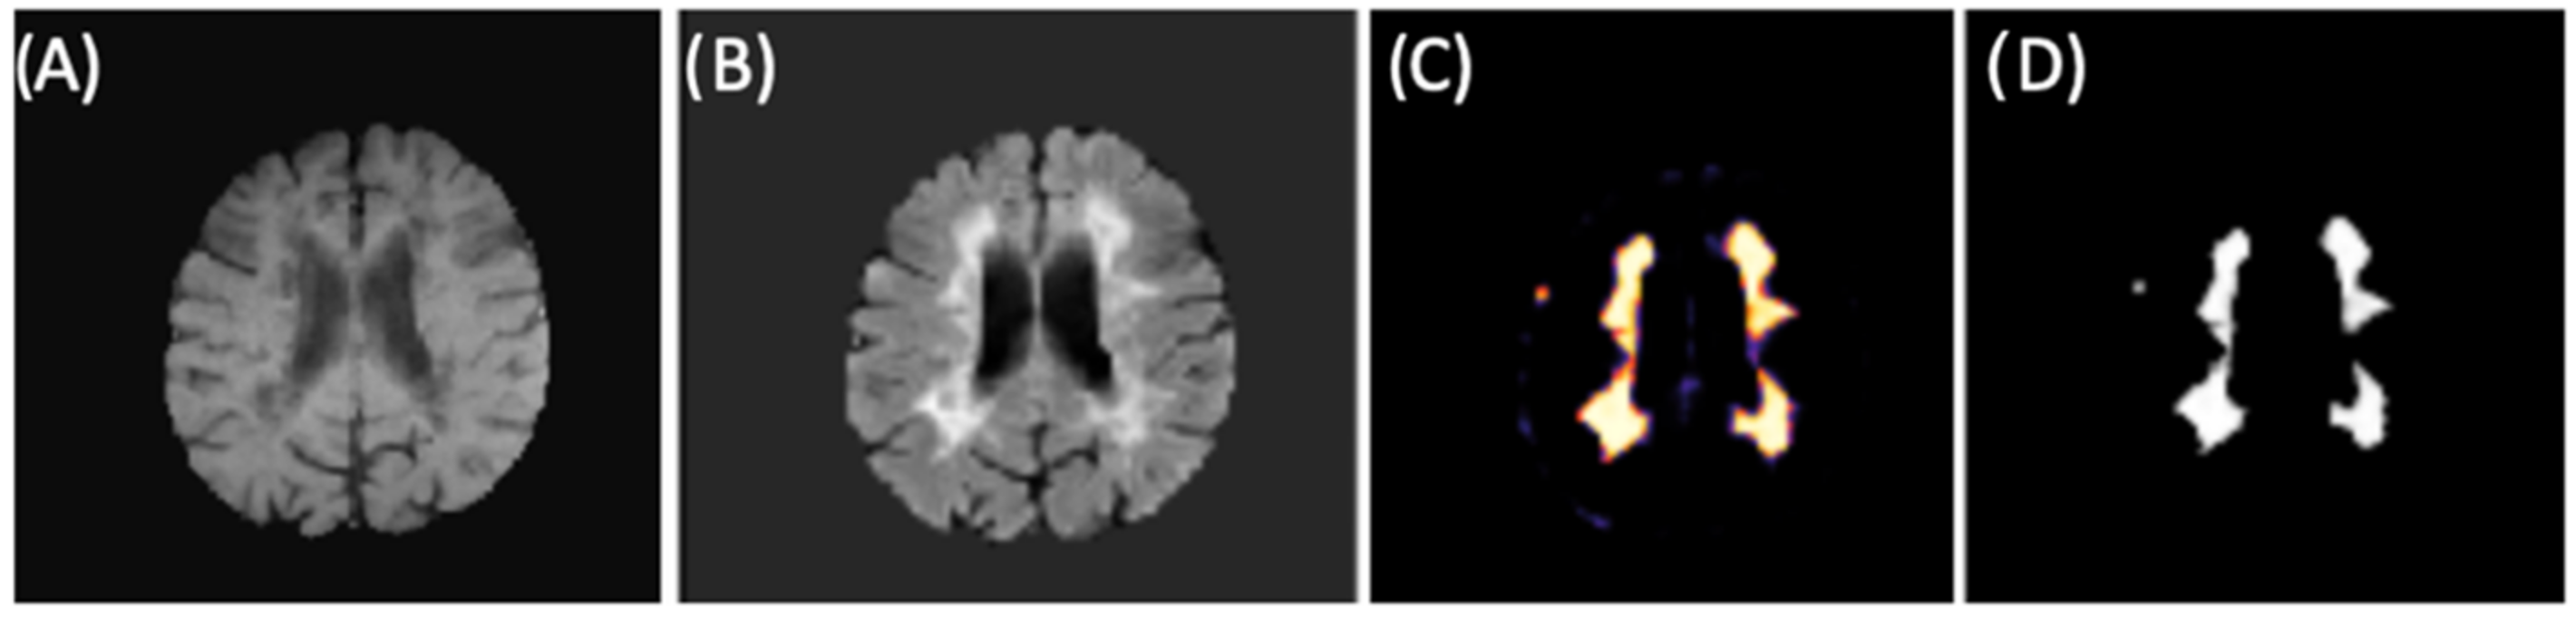

The final training model obtained from the second CNN (as described in Materials and Methods 2.3 and in Figure 2) was used for brain lesion detection, where convolutional blocks were applied to the FLAIR input. From binary mask (outputs), we could detect lesions within new individuals (images) from our test group. Figure 9 shows an example of lesion segmentation on a patient from the test group.

Figure 9.

CNN example for lesion segmentation. (A) T1-w image after preprocessing and brain extraction. (B) FLAIR image after preprocessing and brain extraction (second CNN input). (C) Lesion memberships. (D) Binary mask by thresholding the probabilistic memberships.

Because lesion volume definition is a relevant metric for assessing disease evolution and monitoring treatment, we determined volumetric quantification of the brain lesion by counting the detected voxels from the binary mask (CNN output). After volumetrically quantifying the lesions of all patients from the test group, we obtained a mean value of 17,582 mm3; Figure 10 shows an example where the segmentation was performed on all slices and volumetrically represented.